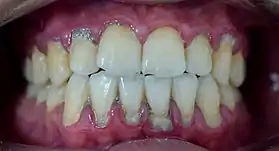

In dentistry, calculus or tartar is a form of hardened dental plaque. It is caused by precipitation of minerals from saliva and gingival crevicular fluid (GCF) in plaque on the teeth. This process of precipitation kills the bacterial cells within dental plaque, but the rough and hardened surface that is formed provides an ideal surface for further plaque formation. This leads to calculus buildup, which compromises the health of the gingiva (gums). Calculus can form both along the gumline, where it is referred to as supragingival ("above the gum"), and within the narrow sulcus that exists between the teeth and the gingiva, where it is referred to as subgingival ("below the gum").

Calculus formation is associated with a number of clinical manifestations, including bad breath, receding gums and chronically inflamed gingiva. Brushing and flossing can remove plaque from which calculus forms; however, once formed, calculus is too hard (firmly attached) to be removed with a toothbrush. Calculus buildup can be removed with ultrasonic tools or dental hand instruments (such as a periodontal scaler).

Plaque accumulation causes the gingiva to become irritated and inflamed, and this is referred to as gingivitis. When the gingiva become so irritated that there is a loss of the connective tissue fibers that attach the gums to the teeth and bone that surrounds the tooth, this is known as periodontitis. Dental plaque is not the sole cause of periodontitis; however it is many times referred to as a primary aetiology. Plaque that remains in the oral cavity long enough will eventually calcify and become calculus.[15] Calculus is detrimental to gingival health because it serves as a trap for increased plaque formation and retention; thus, calculus, along with other factors that cause a localized build-up of plaque, is referred to as a secondary aetiology of periodontitis.

When plaque is supragingival, the bacterial content contains a great proportion of aerobic bacteria and yeast,[18] or those bacteria which utilize and can survive in an environment containing oxygen. Subgingival plaque contains a higher proportion of anaerobic bacteria, or those bacteria which cannot exist in an environment containing oxygen. Several anaerobic plaque bacteria, such as Porphyromonas gingivalis,[19] secrete antigenic proteins that trigger a strong inflammatory response in the periodontium, the specialized tissues that surround and support the teeth. Prolonged inflammation of the periodontium leads to bone loss and weakening of the gingival fibers that attach the teeth to the gums, two major hallmarks of periodontitis. Supragingival calculus formation is nearly ubiquitous in humans,[20][21][22] but to differing degrees. Almost all individuals with periodontitis exhibit considerable subgingival calculus deposits.[15] Dental plaque bacteria have been linked to cardiovascular disease[23] and mothers giving birth to pre-term low weight infants,[24] but there is no conclusive evidence yet that periodontitis is a significant risk factor for either of these two conditions.[25]